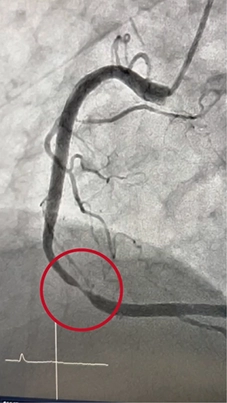

血管造影検査・治療

従来の血管撮影装置よりも、少ないX線量で鮮明な撮影を行なうことができます。心血管検査では一度に広範囲の撮影・診断が可能となり、高精度の検査・治療が行なえます。

また、脳血管検査では脳梗塞の原因となっている血栓の吸引、出血している血管の特定も行なうことができます。

カテーテル検査

検査にはカテーテルという細い管を用いて、血管内に造影剤や薬剤を直接注入することで、狭窄部位や腫瘍などの検索、または治療を行ないます。

心臓カテーテル、血管の3次元画像(3D)など多種にわたって検査することができ、原因疾患の特定にもとても有効な検査です。

検査だけではなく治療も

脳動脈瘤による出血、血栓による脳梗塞、腹部外傷による出血などもカテーテルを使い、わずかな傷で治療を行なうことが可能です。